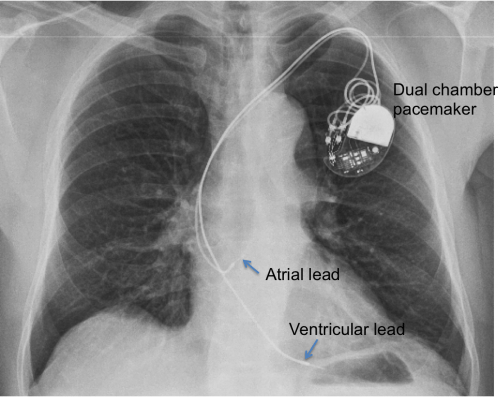

Cardiac pacemaker in situ (441509002) recent clinical studies. A generator and wires (leads). This device senses when your heart is beating irregularly or too slowly.

A Pacemaker Is An Electric Medical Device That’s Generally About The Size Of A Matchbox.